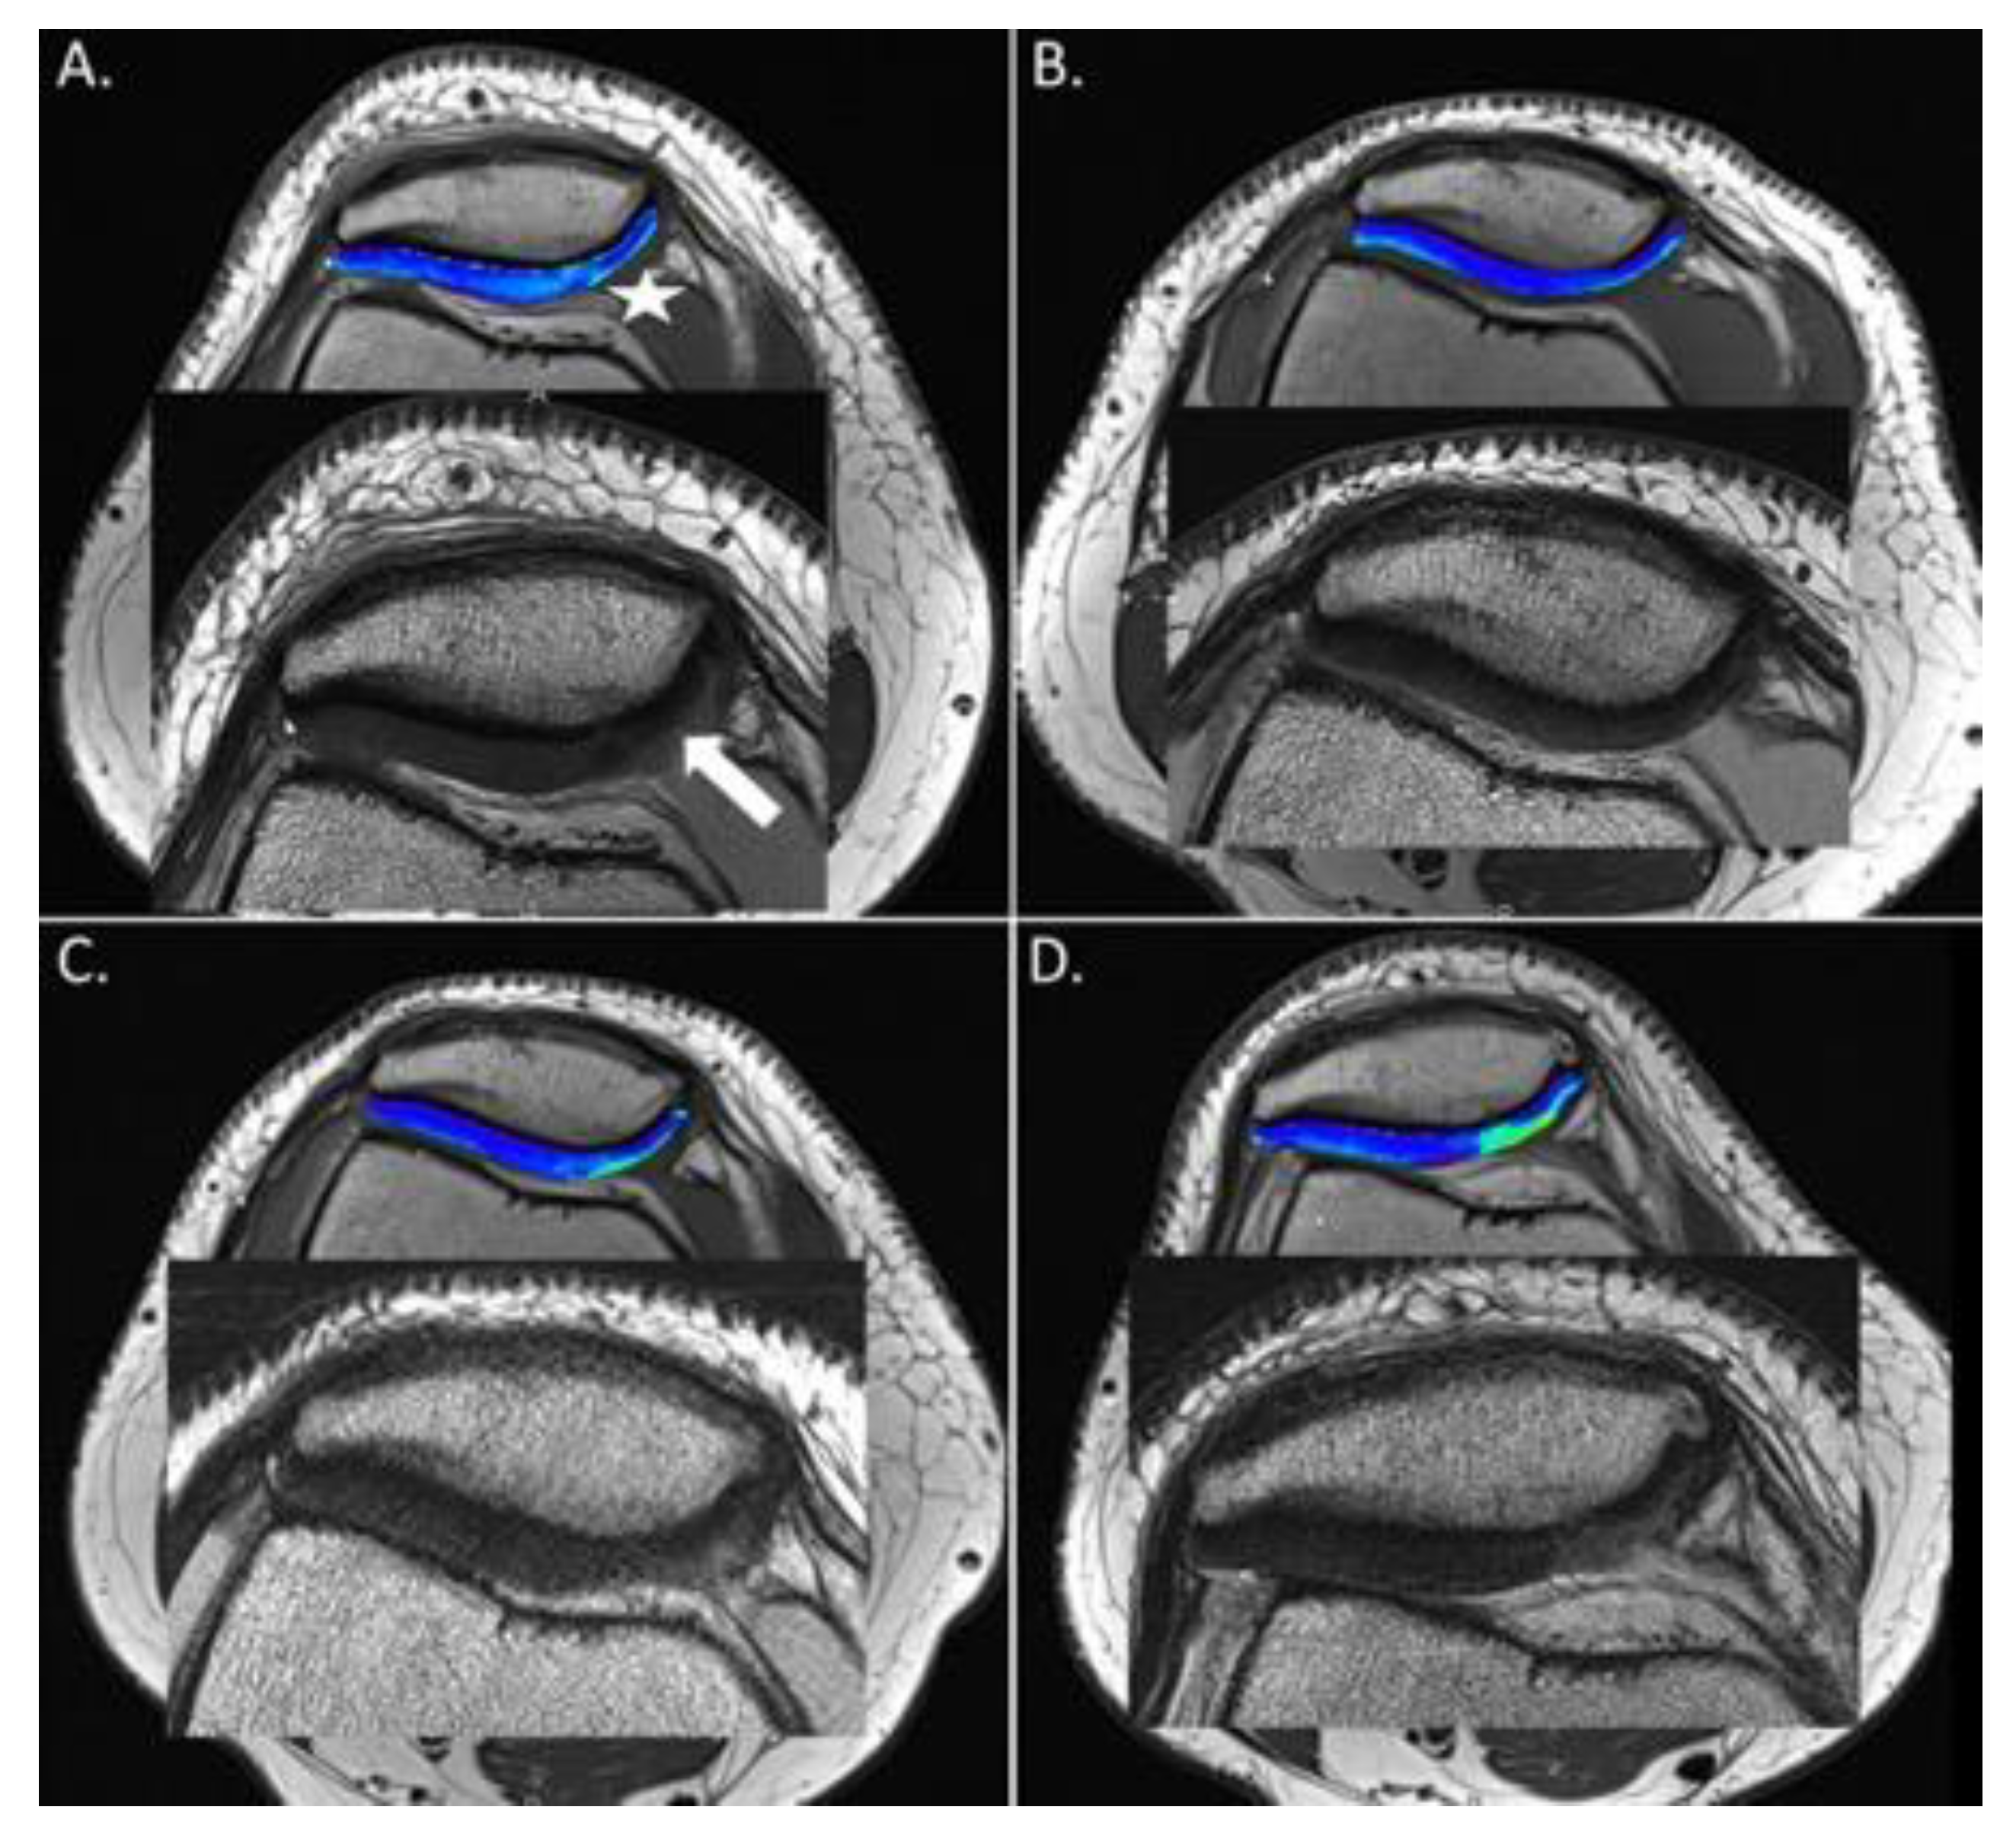

3.4. Morphological MRI